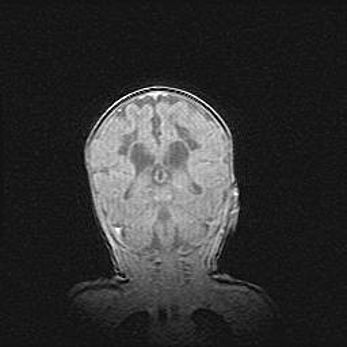

Лейкомаляция с кистозно-глиозной дегенерацией головного мозга.

Возраст: 2 месяца 25 дней

Вес: 6400 г

Окружность головы: 40 см

Срок гестации: 41 неделя

Лейкомаляцию относят к ишемически-гипоксическим повреждениям головного мозга, диагностируемым у новорожденных. При лейкомаляции в головном мозге обнаруживают очаги некроза, возникшие после тяжелой гипоксии и нарушения кровотока. В процессе морфогенеза очаги проходят три стадии: 1) развития некроза, 2) резорбции и 3) формирования глиозного рубца или кисты. Перивентрикулярная лейкомаляция (ПЛ) встречается примерно в 12% случаев среди новорожденных, обычно – у недоношенных детей, причем, частота ее зависит от массы, с которой младенец появился на свет. Наибольшее число малышей страдает лейкомаляцией, если масса при рождении 1500-2500 г.